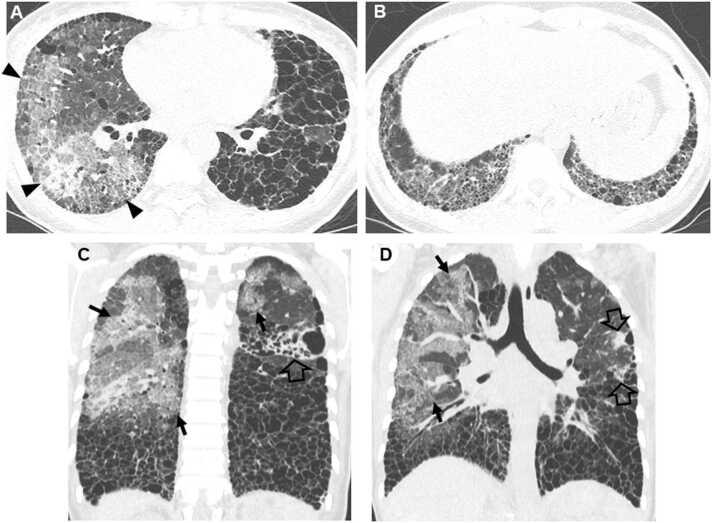

Connective tissue diseases (CTDs) demonstrating features of interstitial lung disease (ILD) include systemic lupus erythematosus (SLE), rheumatoid arthritis (RA), systemic sclerosis (SSc), dermatomyositis (DM) and polymyositis (PM), ankylosing spondylitis (AS), Sjogren syndrome (SS), and mixed connective tissue disease (MCTD). On histopathology of lung biopsy in CTD-related ILDs (CTD-ILDs), multi-compartment involvement is an important clue, and when present, should bring CTD to the top of the list of etiologic differential diagnoses. Diverse histologic patterns including nonspecific interstitial pneumonia (NSIP), usual interstitial pneumonia (UIP), organizing pneumonia, apical fibrosis, diffuse alveolar damage, and lymphoid interstitial pneumonia can be seen on histology in patients with CTD-ILDs. Although proportions of ILDs vary, the NSIP pattern accounts for a large proportion, especially in SSc, DM and/or PM and MCTD, followed by the UIP pattern. In RA patients, interstitial lung abnormality (ILA) is reported to occur in approximately 20-60% of individuals of which 35-45% will have progression of the CT abnormality. Subpleural distribution and greater baseline ILA involvement are risk factors associated with disease progression. Asymptomatic CTD-ILDs or ILA patients with normal lung function and without evidence of disease progression can be followed without treatment. Immunosuppressive or antifibrotic agents for symptomatic and/or fibrosing CTD-ILDs can be used in patients who require treatment.

表现为间质性肺疾病(ILD)特征的结缔组织病(CTD)包括系统性红斑狼疮(SLE)、类风湿关节炎(RA)、系统性硬化症(SSc)、皮肌炎(DM)和多发性肌炎(PM)、强直性脊柱炎(AS)、干燥综合征(SS)以及混合性结缔组织病(MCTD)。在CTD相关ILD(CTD-ILD)的肺活检组织病理学检查中,多部位受累是一个重要线索,若出现这种情况,应将CTD列为病因鉴别诊断的首要考虑。CTD-ILD患者的组织学检查可见多种组织学模式,包括非特异性间质性肺炎(NSIP)、寻常型间质性肺炎(UIP)、机化性肺炎、肺尖纤维化、弥漫性肺泡损伤和淋巴细胞间质性肺炎。尽管ILD的比例各不相同,但NSIP模式占很大比例,尤其是在SSc、DM和/或PM以及MCTD中,其次是UIP模式。据报道,RA患者中约20%-60%会出现间质性肺异常(ILA),其中35%-45%的患者CT异常会进展。胸膜下分布以及基线时ILA受累程度较高是与疾病进展相关的危险因素。无症状的CTD-ILD或ILA且肺功能正常且无疾病进展证据的患者可以不进行治疗而进行随访。有症状的和/或纤维化的CTD-ILD患者若需要治疗,可使用免疫抑制剂或抗纤维化药物。